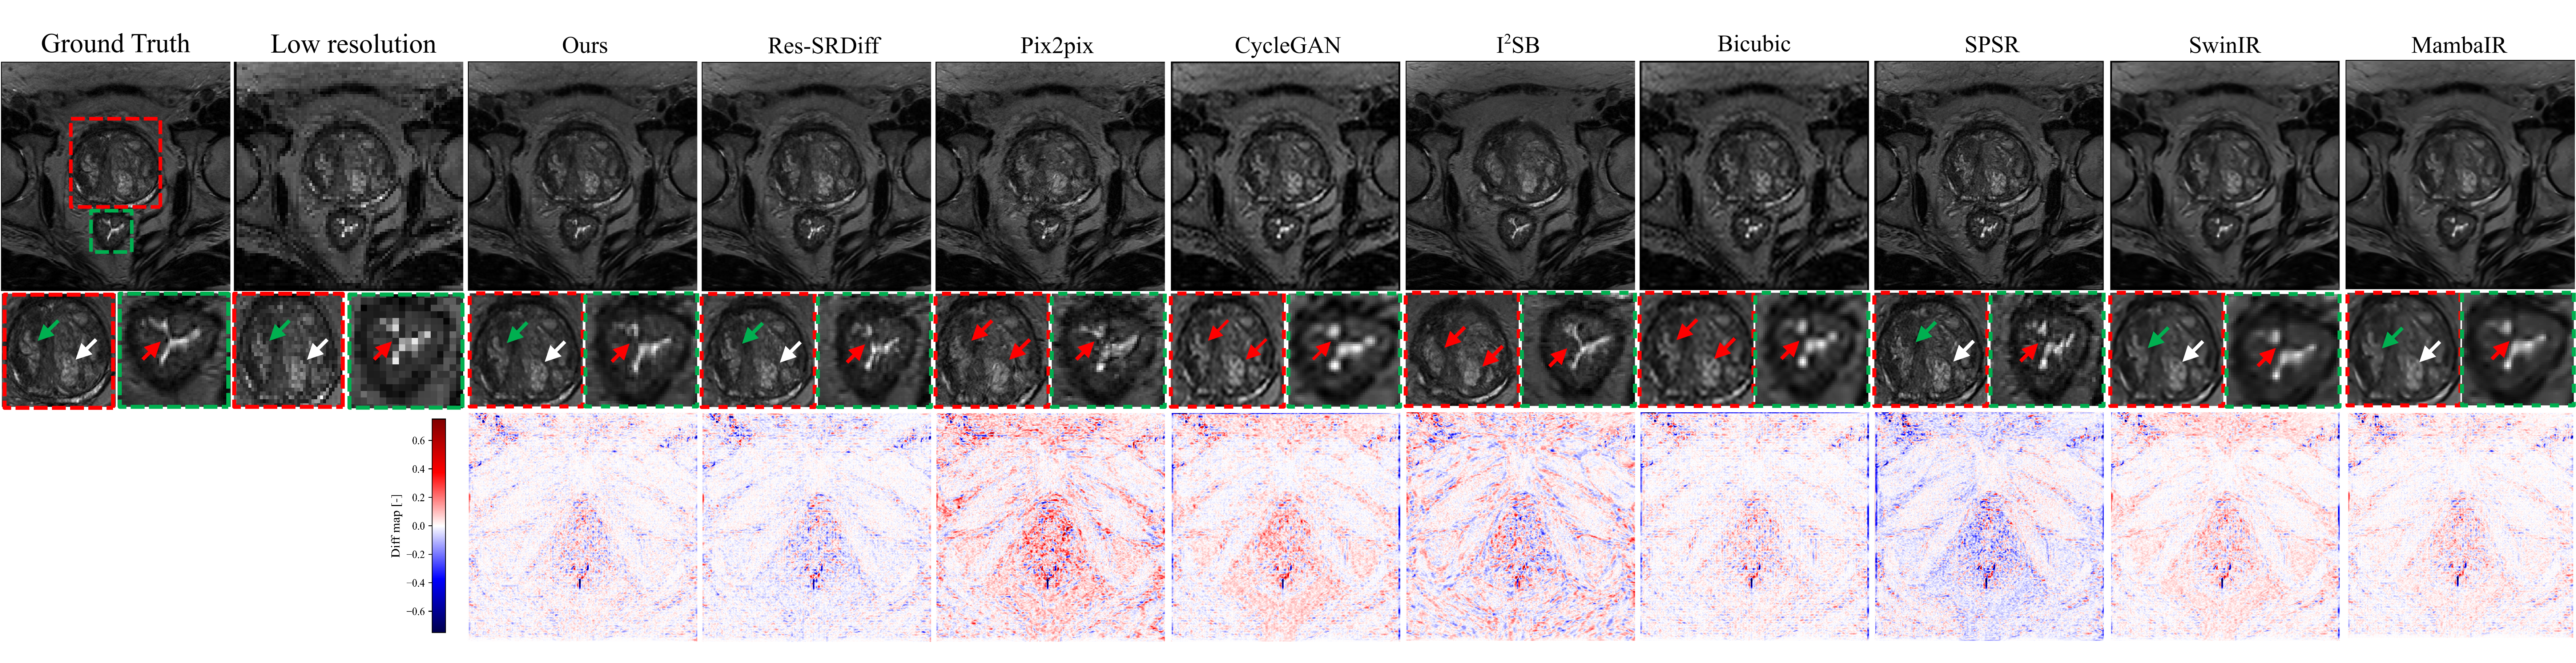

Figure 5 presents a qualitative comparison of super-resolution results on axial T2w pelvic MRI. The ground-truth HR image (leftmost) clearly delineates anatomical boundaries, including the prostate capsule (green arrow), lesion region (white arrow), and surrounding structures (red arrow). Bicubic interpolation fails to recover fine anatomical detail, producing blurred boundaries and oversmoothed textures. GAN-based approaches such as CycleGAN and Pix2pix partially restore high-frequency components but introduce hallucinated structures and amplified noise, as seen in irregular residual patterns. SPSR demonstrates improved texture recovery, although boundary sharpness remains suboptimal. Transformer-based SwinIR shows reasonable global consistency but exhibits edge oversmoothing in fine tissue boundaries, while Mamba-based MambaIR captures local details but occasionally introduces minor artifacts in homogeneous regions. Diffusion-based methods (I2SB and Res-SRDiff) achieve higher fidelity, yet residual artifacts and structural inconsistencies are still visible in lesion-adjacent regions.

Refer to caption

Figure 5: Visual comparison of super-resolution approaches on a representative axial prostate T2w MRI slice. Top panels display the ground truth image together with outputs from competing reconstruction methods. The second row provides magnified views from prostate and bladder regions of interest, chosen to emphasize structural detail. Colored arrows indicate specific aspects under evaluation: green arrows indicate edge delineation of fine tissue, white arrows indicate continuity of anatomical features, and red arrows indicate areas sensitive to artifacts. The bottom panels show voxel-wise difference maps relative to the ground truth.

In contrast, the proposed method reconstructs sharper anatomical edges and preserves tissue continuity, closely matching the ground-truth HR reference. Lesion boundaries and the prostate capsule are more accurately delineated, and residual maps confirm lower reconstruction error relative to competing approaches. These qualitative findings align with the quantitative results summarized in Table 1, demonstrating that our model not only enhances perceptual similarity but also reduces distortion and preserves diagnostically relevant structures.